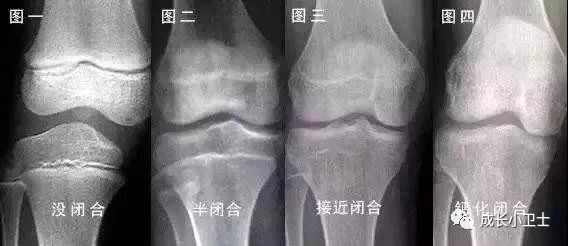

孩子年齡越小,骨骺軟骨層增生及分化越活躍,生長(zhǎng)的潛能和空間越大,一旦骨骺接近或已經(jīng)閉合,就耽誤了最佳治療時(shí)機(jī),任何方案均無(wú)法得到滿意效果。